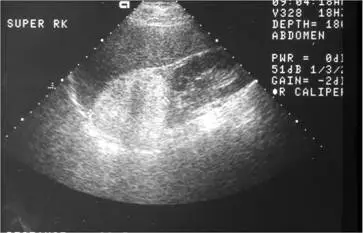

40 歲男性病⼈因上腹部不適,上腹部超⾳波檢查發現右腎上⽅腫瘤如圖,最可能的診斷為何?

本題圖片為腹部超音波(標記 SUPER RK,即右腎上方區域),可見:

- 位置:右腎上方、腎上腺區域,可見一邊界清楚的腫塊

- 回聲特性:腫瘤呈現均勻強回聲(homogeneous hyperechoic),明顯較周圍組織亮

- 邊界:腫瘤邊緣清晰規則,與鄰近腎臟有明顯分界

- 無聲影:不像腎結石會產生後方聲影,此腫瘤後方無明顯聲影

影像判讀意義:超音波強回聲腫塊位於腎上腺區域,最典型的診斷就是腎上腺髓脂瘤——因為腫瘤富含脂肪,超音波下脂肪組織回聲強,造成此特徵性強回聲表現。文獻報告超音波診斷髓脂瘤的敏感度達 89%、特異度 99%。